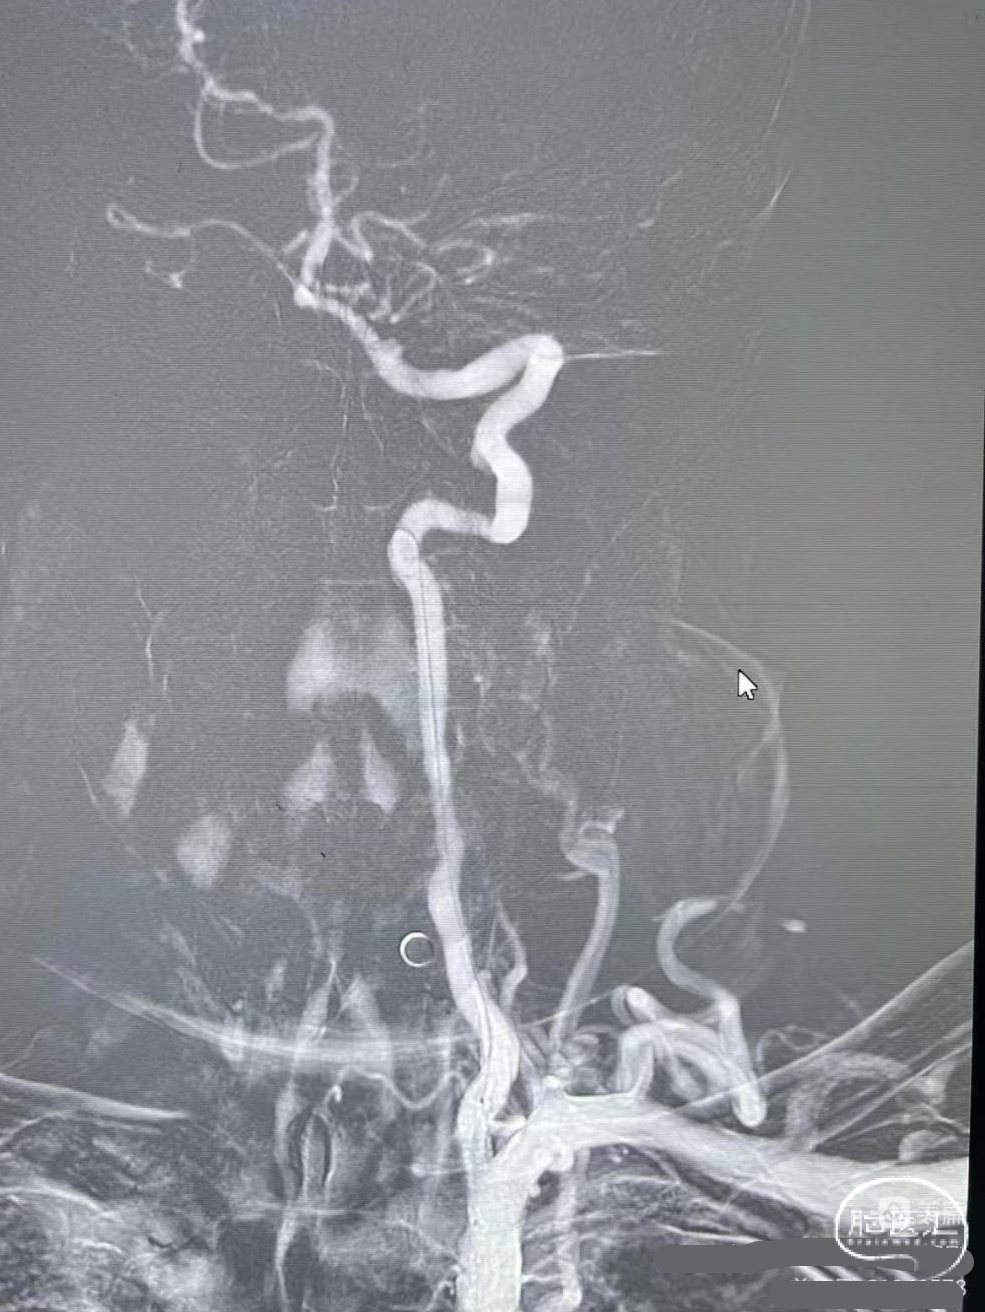

术后造影:

血管再通,前向血流3级。左侧为胚胎型大脑后。

术后CTA:Bridge药物支架形态良好,前向血流良好。

术后半年CTA:Bridge支架形态及贴壁良好,前向血流正常。